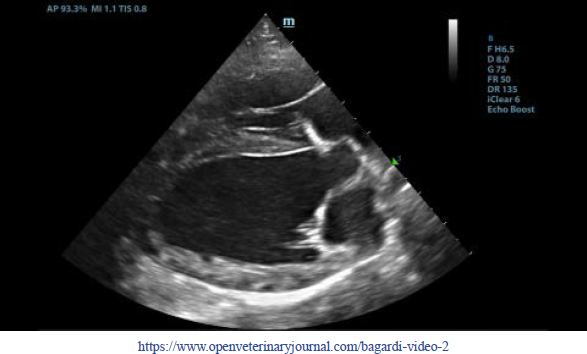

First, transthoracic echocardiogram findings were a small amount of circumferential tamponating pericardial effusion (Fig. 1) and a severe hyperechoic pericardial thickening (10.2 mm) (Fig. 2). The right atrium was normal in size and there was collapse during systole. There was mild septal flattening seen on short axis view of the left ventricle. A short-axis left ventricular M-mode showed posterior displacement of the interventricular septum during late diastole at the time of atrial systole (Fig. 3). The epicardium and pericardium had a hyperechoic appearance with a thin, shaggy layer of heterogeneous echogenic material lining the surface of each (Fig. 1, Supplementary Video I). Pericardiocentesis was not recommended at this time given that the patient was minimally clinically and hemodynamically affected. Few hours later, a second echocardiographic examination, after stabilization of left ventricular volume with intravenous (IV) lactate ringer solution at maintenance rate, showed a worsening of pericardial thickness (13 mm) and an increase in pleural effusion. Furthermore, there was a >25% mitral inflow variation noted with respiration. In addition, there was >30% tricuspid inflow variation with respiration, signs of CP. During the second echocardiography, the patient appeared to be slightly dyspneic due to the increased thoracic effusion.

Fig. 2. Transthoracic echocardiogram – left apical five-chambered view. Note the pericardial effusion (white arrowhead) and the severe pericardial thickening (white arrow). Ao: aorta; LA: left atrium; LV: left ventricle; RA: right atrium; and RV: right ventricle.